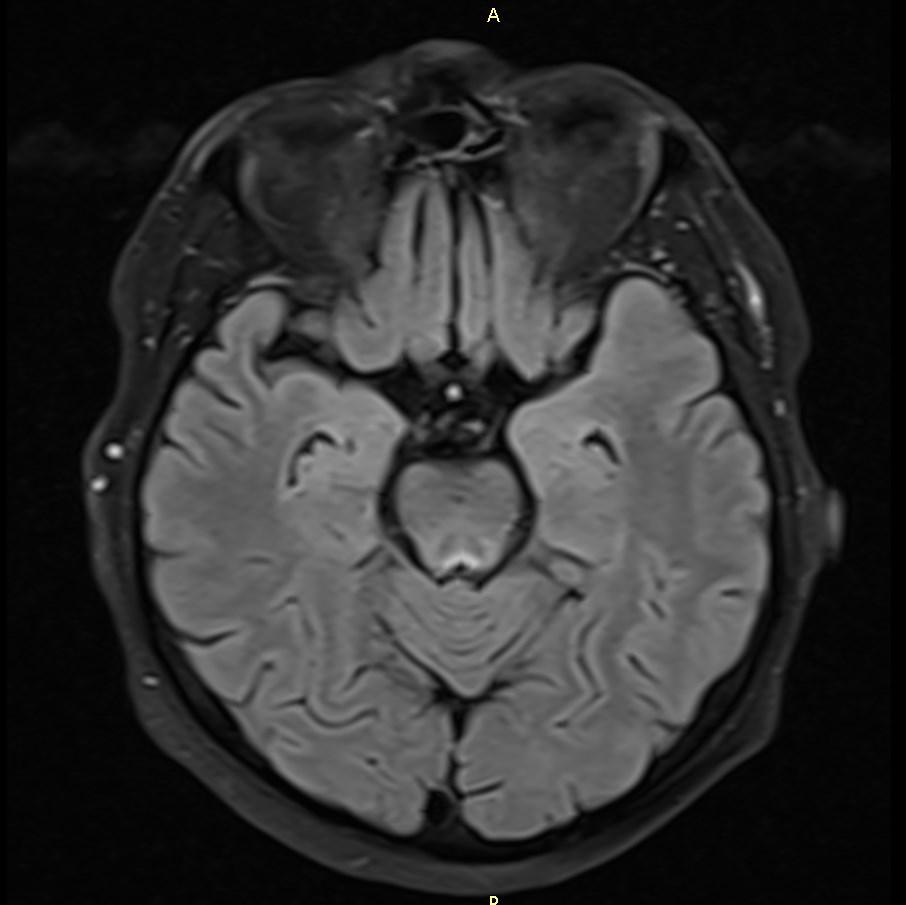

MRI images revealed hyperintensities in the periaqueductal region and the medial thalami.

T2/FLAIR: symmetrically increased signal intensity in the mamillary bodies, dorsomedial thalami, tectal plate, periaqueductal area, and around the third ventricle.